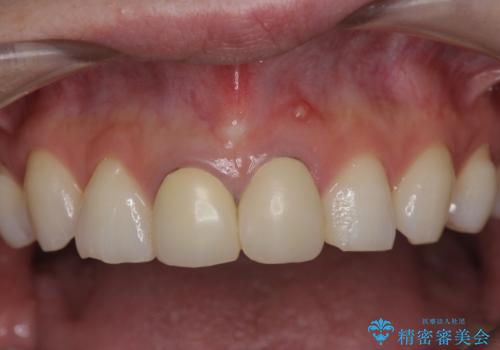

前歯が疼く セラミッククラウンのやり替え

- 「幼少期に転んで治療した前歯がうずく、疲れると膿が出る。」と治療を希望され来院されました。

X線写真検査に加え圧痛、打診痛が認められたため、慢性根尖性歯周炎と診断し、根管治療から行うセラミック治療を計画します。